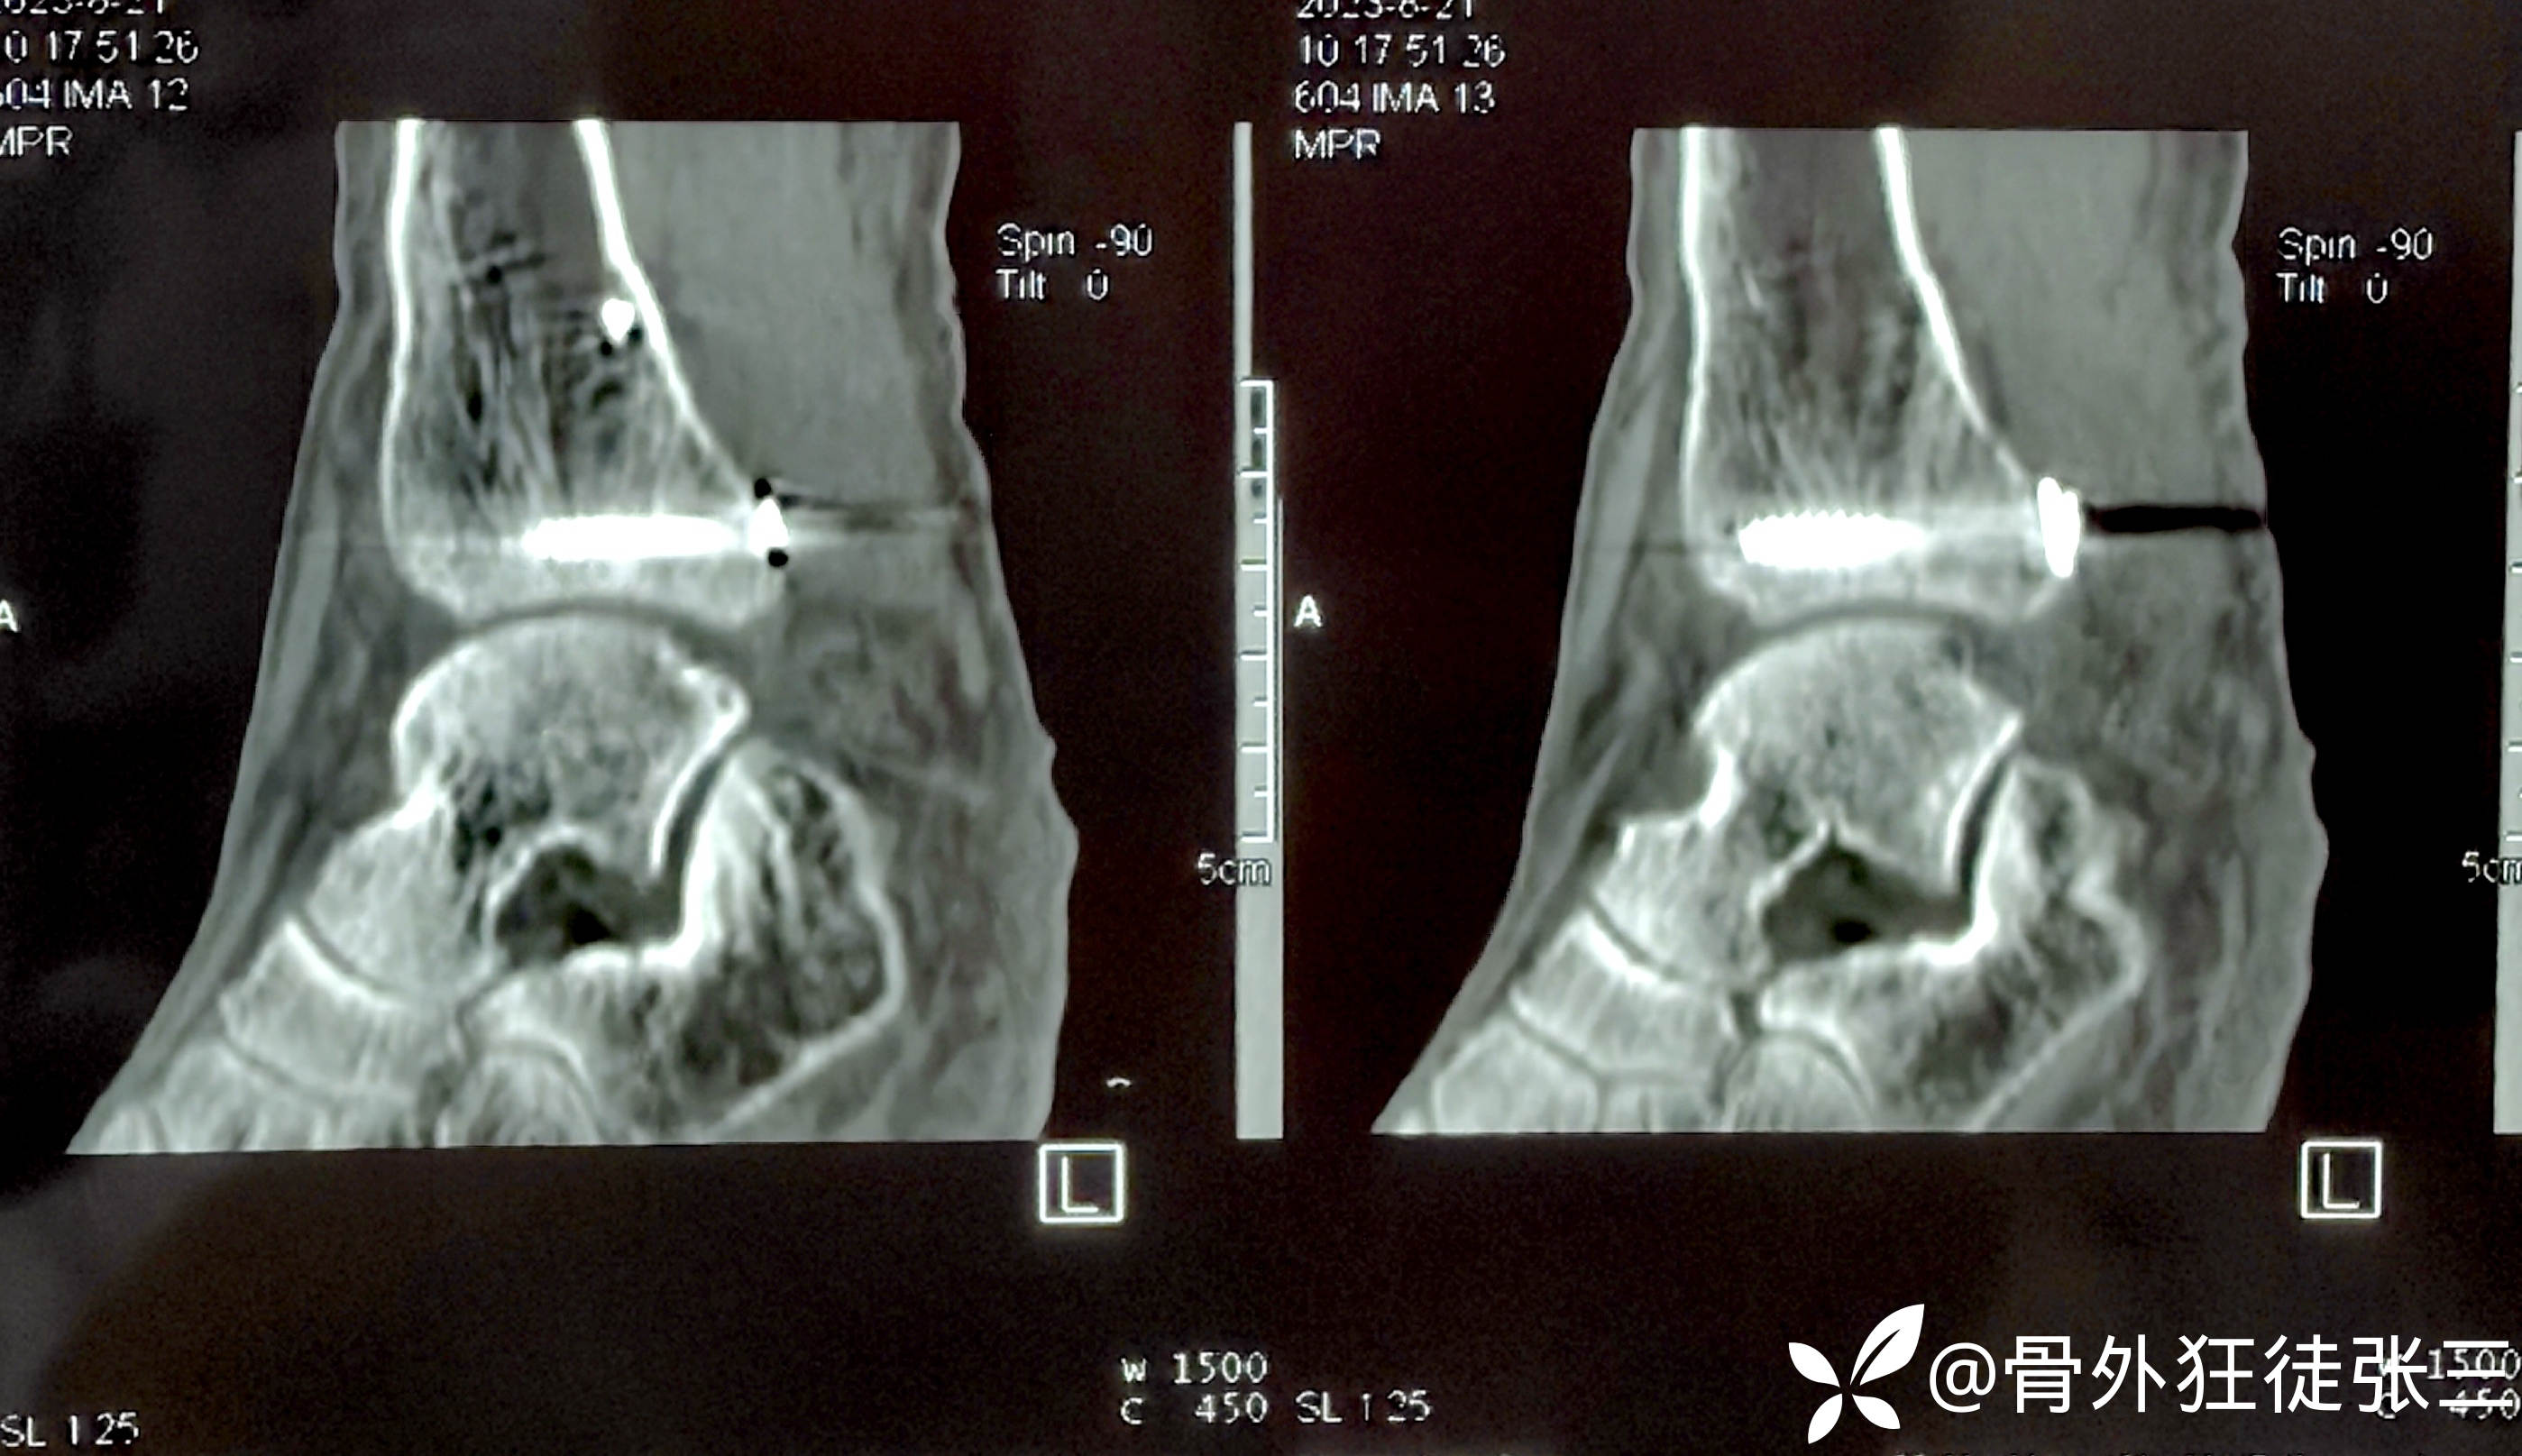

术后CT验证

后踝骨折复位良好

下胫腓位置良好

内踝骨折位置良好。